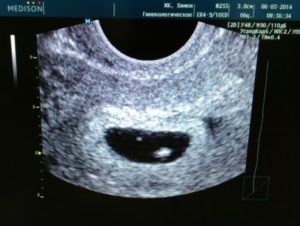

Что касается ультразвуковой визуализации развивающегося внутриутробно человека, то на стадии 4 акушерских недель возможно увидеть только лишь плодное яйцо. В период 5-6 акушерских недель возможно зарегистрировать сердцебиение эмбриона. Отчётливо эмбрион в виде буквы С может быть идентифицирован в матке на уровне 7-8 недель.

Пока же можно только рассмотреть на УЗИ, как внешне выглядит плодное яйцо.

Измерение/Способ Трансабдоминально Трансвагинально

Диагностика маточной беременности, недель 5–6 4–5

Визуализация эмбриона, недель 6 5

Движения эмбриона, недель 7–8 5–6

Сердечная деятельность, недель 6–7 5–6

В том случае, если у женщины регулярный менструальный цикл, то при трансвагинальном УЗИ распознавание эмбриона происходит не позднее 6 недель. Если же цикл непостоянный, то определить точный срок по месячным нельзя.

Сердечная мышца эмбриона начинает сокращаться с 3 недель и 4 дней. Уловить стук сердца лучше с помощью вагинального датчика. Иногда бывает, что на этом сроке ничего в яйце не видят, тогда рекомендуют прийти еще одно УЗИ примерно через неделю, а то и две. Частота сердечных сокращений (ЧСС) позволит уточнить срок беременности.